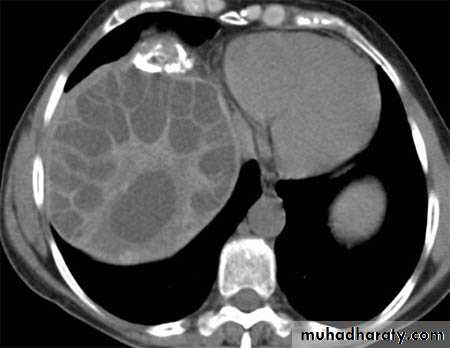

Hydatid cyst

Appear as large oval hypo dense area density of fluid with well defined margin , sometime at their periphery multiple flecks of calcification are seen at their periphery .

Hydatid cyst with daughter cyst , appear as multiple hypo densities rounded area within the main loculi with multiple rim of

calcification

Hydatid cyst within the liver

CT Scane